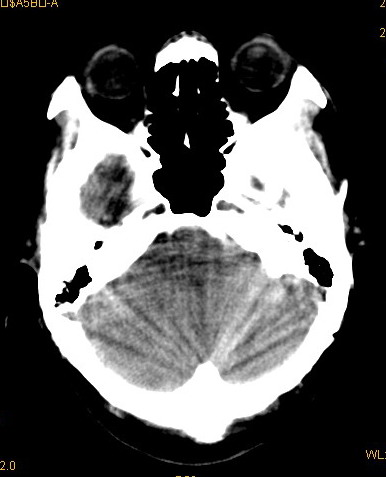

以下是引用卜一在2008-8-14 16:31:00的发言:[br]支持:巨脑回伴脑积水!另:胼胝体发育不良!

以下是引用同在2008-8-14 19:46:00的发言:[br]巨脑回伴积水,胼胝体发育不良.